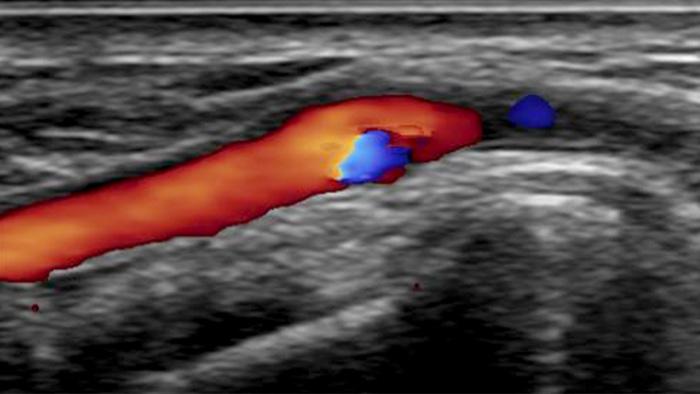

Uma visualização realista da vasculatura arterial é necessária para acessar o sistema arterial com eficácia. Nosso sistema de ultrassom integrado CX50 fornece imagens de qualidade premium da artéria radial e das veias para facilitar intervenções de acesso radial.